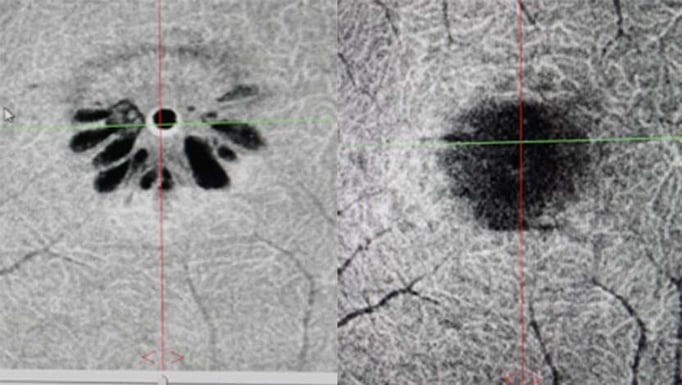

ilm staining with icg in macular hole surgery a the green stained download scientific diagram